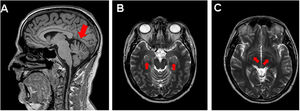

Few studies include neuroimaging assessment of patients with post–COVID-19 cognitive impairment. MRI scans of COVID-19 patients after hospital discharge have detected such findings as increased signal intensity and increased mean diffusivity in the thalamus, as well as periventricular white matter hyperintensity. (38) In our experience, dilation of perivascular spaces in the hippocampus and basal ganglia is occasionally observed in these patients (Fig. 2). These findings may correspond to perivascular inflammation in histopathological studies. (49)